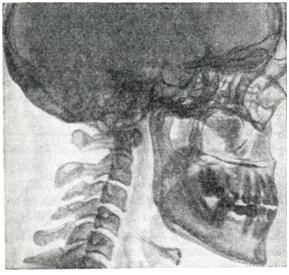

Межпозвоночные диски гипертрофируются и в то же время подвергаются дистрофическим изменениям, сопровождающимся разрывами хрящевых пластинок с образованием грыж Шморля и деформирующего спондилеза. Трубчатые кости увеличиваются преимущественно в ширину путем периостального аппозиционного роста. Костномозговой канал расширяется за счет рассасывания кости и эндостальной поверхности. Таким образом, особого увеличения массы костей не происходит. Удлинение костей больше заметно в кистях и стопах, что связано с возобновлением энхондрального роста в области хрящей фаланг. Костные разрастания выражены главным образом в местах прикрепления сухожилий, фасций, они усиливают нормальные бугристости, гребешки. Этим акромегалия, отличается от сходных с ней гиперостозов при синдроме Мари — Бамбергера (смотри Бамбергера— Мари периостоз). Микроскопические изменения костей выражаются в интенсивной перестройке костной ткани. В кортикальном слое резко увеличено количество остеонов, много так называемых обломков остеонов. В губчатых отделах разрежение структуры, но сами костные балки толще обычного. Изменения суставных хрящей выражаются в пролиферативных и дистрофических процессах. Пролиферативные процессы, возникающие под влиянием усиленного выделения гормона роста, приводят к образованию молодого хряща. Физические свойства межуточного вещества такого незрелого хряща не соответствуют испытываемой им механической нагрузке. Поэтому в нем развиваются дистрофические изменения. Длительное чередование пролиферативных и дистрофических процессов приводит к развитию деформирующего артроза, особенно выраженного в крупных суставах. В краевых зонах суставных концов костей происходит возобновление энхондрального роста кости с образованием краевых костных утолщений. В синовиальной оболочке могут быть ворсинчатые выросты, участки хрящевой и костной тканей. Аакромегалия, может сопровождаться изменениями других эндокринных желез: зобом, атрофией инсулярного аппарата, гиперплазией шишковидной и зобной желез, коры надпочечников, атрофией гонад. Описаны случаи сочетания акромегалии, с паратиреоидной остеодистрофией, с феохромоцитомой надпочечника. В более поздних стадиях болезни развиваются атрофические изменения мышц. Патогенез.Доказано, что развитие акромегалии, связано с нарушением регуляции соматотропной функции гипофиза через продуцируемый гипоталамусом соматотропин-рилизинг-фактор (смотри Гипотлламические нейро гормоны), что приводит к избыточному выделению из гипофиза гормона роста (смотри Соматотропный гормон). Повышение соматотропной функции гипофиза, Вызывающее развитие акромегалии,, может быть при эозннофильной аденоме, аденокарцпноме и при других опухолях гипоталамуса и гипофиза, а также при функциональных нарушениях в гипоталамо-гипофизарной системе. Избыточная секреция соматотропного гормона у взрослых, у которых процесс роста костей закончен, обычно вызывает акромегалию. В детском и юношеском возрасте при незакрытых эпифизарных зонах роста повышенное выделение соматотропного гормона чаще обусловливает развитие гигантизма. Клиническая картина.Акромегалии развивается постепенно; иногда отдельные симптомы заболевания появляются в раннем возрасте. Заболевание характеризуется прежде всего непропорциональным ростом и изменением формы лица (рис. 1). Нос становится толстым, надбровные дуги вследствие увеличения пневматических полостей значительно выступают вперед; скулы увеличены, нижняя челюсть выдается вперед, нижняя губа вздувается. Вследствие разрастания нижней челюсти между зубами образуются промежутки — так называемая диастема. Отмечается также рост ушей. Очень характерен симптом макроглоссии — большой язык. Нередко наблюдается рост язычка и голосовых складок — голос становится низким. На черепе резко выступают височные бугры и кости черепной крыши. Голова значительно увеличена как за счет утолщения мягких тканей волосистой части головы, что приводит к образованию грубой складчатости на затылке, так и за счет наслоения костной ткани.

Очень характерны изменения на дистальных частях конечностей. Обычный тип акромегалии — это так называемый «type en large» (Мари), характеризующийся лопатообразным расширением кистей и стоп, широкими пальцами (рис. 2) с выступающей пяточной костью. Разрастаются главным образом мягкие ткани рук и стоп. На фалангах нередко наблюдаются экзостозы. Больные вынуждены часто увеличивать размер обуви, перчаток. Реже, преимущественно у больных с незаконченным ростом скелета, наблюдается «type en long», когда руки и стопы вытянуты в длину. Грудина, ключицы, ребра чрезмерно развиты. На грудной клетке нередко наблюдается шейно-спинной кифосколиоз и лордоз в поясничной области. Кожа у большинства больных утолщена, образует складки, обычно сухая, реже отечная. Часто наблюдаются фибромы, бородавки. Волосы на голове и бровях толстые, жесткие, густые. На конечностях и туловище наблюдается гипертрихоз; особенно резко он выражен у женщин на лице. Растительность на теле у женщин распределяется чаще по мужскому типу, что, по-видимому, связано, особенно на ранних этапах болезни, с усилением функциональной активности у этих больных системы гипоталамус — гипофиз — кора надпочечников. Спланхномегалия у больных акромегалией встречается очень часто (кардиомегалия, гепатомегалия, спленомегалия и другое). Не менее чем в 60—80% случаев отмечается атрофия половых желез, аменорея, понижение полового влечения и половая слабость (в начале заболевания, наоборот, может наблюдаться повышение полового влечения и половых функций). Атрофии наружных половых органов не наблюдается, в начале болезни иногда отмечается даже их увеличение. У больных акромегалией имеются признаки повышенного внутричерепного давления: головные боли, головокружения, рвота, реже эпилептоидные припадки. У многих больных акромегалией наблюдаются расстройства зрения, которые чаще являются следствием давления опухоли на хиазму и зрительные нервы, в связи с чем для акромегалии характерна битемпоральная гемианопсия, начинающаяся обычно с верхнего внешнего квадранта, часто в виде парацентральной скотомы. При асимметрическом расположении хиазмы наблюдаются односторонние ге-мианопсии. Если увеличение гипофиза происходит в сторону клиновидной кости, то резких расстройств зрения у больных не отмечается. Для диагностики и наблюдения за течением болезни нужно производить периметрию. Иногда гемианопсии предшествует ахроматопсия, поэтому необходимо производить периметрию и на цвета. Со стороны нервной системы обнаруживаются боли, особенно в спине, акропарестезии, невралгии, связанные с давлением разрастающихся костей и деформированных позвонков на нервные пути и корешки. Кровяное давление часто повышено, по-видимому, за счет активизации функции коры надпочечников. В более поздних стадиях заболевания в мышцах находят дегенеративно-атрофические изменения, с чем связана повышенная утомляемость. У больных акромегалией нарушен углеводный обмен. По данным Давыдова, у 12% больных акромегалией отмечается сахарный диабет, а у 25% — нарушения глюкозотолерантности. Стойким симптомом акромегалии следует считать полифагию, менее частыми — полидипсию), иногда связанную с несахарным диабетом, и полиурию. В периферической крови у больных акромегалией, кроме некоторого лимфоцитоза и эозинофилии, существенных отклонений не имеется. Кроме того, выделяют доброкачественную и стертую форму акромегалии. При доброкачественной акромегалии не наблюдается нарушения зрения и функции половых желез. У больных отмечается главным образом гипертрихоз, гипергидроз, усиленная деятельность сальных желез, приводящая к появлению угрей на коже, большой язык, плохо умещающийся в полости рта. Очень характерны головные боли, алиментарная гликозурия. При стертой форме акромегалии (forme fruste) патологический процесс протекает очень медленно. При этой форме заболевания для больных характерны большие уши, длинное и крупное лицо. Они страдают головными болями, преимущественно ночью, бессонницей, у них может быть фиброматоз, гипертрихоз и некоторые другие проявления, характерные для акромегалии. Во время полового созревания иногда наблюдается огрубение черт лица и увеличение выступающих его частей; с возрастом эти признаки постепенно сглаживаются. Преходящей формой является и акромегалия беременных, дающая иногда толчок для развития истинной акромегалии. При акромегалии. беременных изредка отмечается битемпоральная гемианопсия. Отдельные авторы полагают, что среди здоровых людей встречаются лица с акромегалоидной конституцией; это люди высокого роста, с крупными костями, большой челюстью, выступающими надбровными дугами, крупными черепом, носом, губами и конечностями. Под влиянием неблагоприятных воздействий эта конституциональная форма может перейти в истинную акромегалию (описаны случаи акромегалии после удаления матки). Существует частичная (парциальная) акромегалия, поражающая только язык, пальцы, стопу и тому подобное. Эти изменения можно объяснить повышенной чувствительностью отдельных тканей у данных индивидуумов к соматотропному гормону гипофиза. Нередко акромегалия сочетается с тиреотоксикозом, микседемой, адипозо-генитальной дистрофией и патологией надпочечников. На ранних этапах болезни функция коры надпочечников может быть повышена, а щитовидная железа увеличивается. В поздних стадиях болезни функция этих желез может снижаться. Психические расстройства.В психопатологическом аспекте различают истинную А. и акроме-галоидную конституцию [Блейлер (М. Bleuler)!. Психические наруше¬ния, наблюдаемые у людей с акромегалоидной конституцией, те же, что и при истинной акромегалии, но значительно менее выражены. Акромегалия сама по себе психозов обычно не вызывает. Однако в большинстве случаев у больных развиваются характерные изменения личности (своеобразный вариант эндокринного психического синдрома) или, при особенно неблагоприятном течении заболевания, амнестически-органический синдром. На фоне психических сдвигов, входящих в рамки этих синдромов, могут развиваться симптоматические психозы, обусловленные, как правило, тяжелыми соматическими расстройствами (повышением внутричерепного давления, нарушениями обмена и тому подобным). Психозы могут быть галлюцинаторно-параноидными, депрессивно-ипохондрическими, типа острой экзогенной реакции. Существовавшая ранее точка зрения об особой частоте шизофреноподобных психозов и психозов типа маниакально-депрессивного, а также о связи акромегалии с шизофренией и маниакально-депрессивным психозом при специальных исследованиях не подтвердилась (Блейлер и другие). В эндокринном психическом синдроме при акромегалии достаточно ярко выражены все три компонента: снижение психической активности, расстройство настроения и расстройство влечений. Снижение психической активности клинически обычно проявляется апатией, вялостью, аспонтанностью, отсутствием инициативы, реже психомоторной заторможенностью. Описанные изменения сочетаются с благодушно-эйфорическим настроением и чувством пассивной самоудовлетворенности. Легкая эйфория и благодушие могут наблюдаться у больных даже при сильных головных болях и сонливости. В отличие от эйфории при маниакально-депрессивном психозе, у больных акромегалией она не сопровождается двигательной гиперактивностью. Наблюдаются также и депрессивные состояния с тревогой, ворчливостью, напряженностью и плаксивостью. Характерны для акромегалии беспричинные колебания настроения на протяжении короткого времени. Из расстройств влечений встречаются выраженные колебания аппетита (периодическое резкое усиление аппетита, появление жажды), снижение либидо, повышение потребности в сне и иногда приступы сонливости. Могут быть также периоды повышенной двигательной активности, носящей характер импульсивности. В отношениях с окружающими больные могут проявлять повышенную ранимость, нетерпеливость, раздражительность, эгоцентризм. При наличии эндокринного психического синдрома значительного снижения интеллекта не бывает; замедленность психических процессов и некоторое снижение круга интересов, как правило, не мешают таким больным продолжать трудовую деятельность. При выраженных гормональных сдвигах (повышение продукции лактотропного гормона и другого) могут наблюдаться своеобразные изменения поведения, так называемое поведение матери (повышенное внимание к детям, забота о них с выполнением разнообразных материнских обязанностей). Подобные изменения поведения наблюдаются не только у женщин, но и у мужчин. Если развивается амнестическо-органический синдром, то он проявляется расстройствами памяти, снижением критики и интересов, огрубением личности, бестактностью. Описаны исходы в своеобразный аутизм с угрюмой ворчливостью. Смотри также Эндокринные психические синдромы. Диагноз и дифференциальный диагноз.Диагноз акромегалии не представляет особых затруднений и ставится на основании достаточно выраженного комплекса симптомов. Изменения скелета при акромегалии до такой степени характерны, что уже по одному внешнему виду можно ставить диагноз. Из специфических лабораторныхдиагностических исследований имеют значение (особенно в случаяхстертой формы акромегалии) исследования содержания соматотропного гормона (СТГ), неорганического фосфора инеэтерифицированных жирных кислот в крови. По данным М. И. Балаболкина (1966), концентрация соматотропного гормона в крови больных акромегалией составляет 37,51 + 10,72 мкг%, в то время как в норме уровень соматотропного гормона в крови равен 18,37 + 6,21 мкг%. Содержание неорганического фосфора повышено (выше 4,5 мг%) у подавляющего большинства больных; не менее часто отмечается повышение содержание неэтерифицированных жирных кислот (выше 850 мэкв/л). Акромегалию необходимо дифференцировать с болезнью Педжета, при которой поражаются главным образом свод черепа и диафизы длинных костей, при акромегалии же — лицо и пальцы (смотри Остоз деформирующий); с парциальным гигантизмом, общим гигантизмом, синдромом Мари— Бамбергера. Рентгенодиагностика акромегалии способствует уточнению диагноза. Рекомендуется произвести обзорные снимки черепа в боковой и лобной проекциях и прицельные рентгенограммы турецкого седла. Боковая томограмма, сделанная через срединную сагиттальную плоскость черепа, способствует получению более точной информации о состоянии турецкого седла. Еще в ранней фазе заболевания, когда отсутствуют выраженные эндокринные расстройства, возникают изменения турецкого седла в виде выпрямления спинки, истончения ее основания и склерозирования верхней ее части. В выраженных случаях акромегалии череп большого размера. Особенно увеличен лицевой скелет (рис. 3). Рентгенологическая картина мозгового черепа приобретает пестроту в связи с перестройкой костного рисунка с преобладанием гиперостоза и утолщением диплоэ. Увеличиваются придаточные пазухи, особенно лобные. Клиновидная пазуха суживается за счет продавленности дна гипофизарной ямки. Деформируется турецкое седло: сагиттальные и вертикальные размеры увеличиваются в несколько раз, дно опускается, спинка отклоняется, истончается у основания, но рисунок верхушки спинки и прилегающей зоны усиливается за счет уплотнения костной структуры. Задние наклоненные отростки загибаются кпереди; в связи с этим на боковом снимке вход в седло кажется суженным. Контур гипофизарной ямки становится разреженным, исчезает изображение каймы компактного слоя. Следует учитывать возможность распространения опухоли вверх или в какую-нибудь сторону. Последнее выявляется по истончению и смещению на лобном снимке переднего наклоненного отростка на стороне поражения.